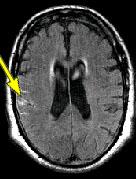

IMAGING FINDINGS: The CT was performed on AIC’s new 16-slice helical multi-slice CT (MSCT). Both routine single-slice and thin-section helical scans were obtained and 3D/Multiplanar images were performed on the Advanced 3D workstation. Fig. 1 shows an image at the level of the lateral ventricles with possible high density within the sulci on the right (arrow). To confirm this finding, an MRI with contrast was then obtained on AIC’s 1.5-Tesla high-field, short-bore Siemens MRI. Fig. 2a-b are T2-weighted images at the same level showing NO definite abnormality. T1-weighted images (not shown) were also negative. The post-contrast images (not shown) showed NO abnormal enhancement in this region, either. Diffusion-weighted images were also negative. However, Fig. 3a-b, which are FLAIR images, demonstrate clear hyperintensity within multiple sulci involving the right temporo-parietal area (arrows).

DIAGNOSIS: The FLAIR images are compatible with Subarachnoid disease. The Differential Diagnosis includes: (1) Subarachnoid Hemorrhage (SAH); (2) Meningitis; (3) Infarct; (4) Flow Artifact. Lack of enhancement is against meningitis. Acute infarct was ruled out on the basis of negative Diffusion MRI and lack of cytotoxic edema on the FLAIR images. Focal abnormality is against flow artifact (which is more diffuse and usually in the posterior fossa on FLAIR images). The clinical history of trauma and the high-density on CT and hyperintensity on FLAIR images within the sulci are diagnostic of Acute Post-traumatic Subarachnoid Hemorrhage (SAH).

DISCUSSION: MRI FLAIR imaging is the modality of choice for diagnosis of supratentorial SAH. In the posterior fossa, however, CT is superior due to flow artifacts on FLAIR images in the peripontine/ambient cisterns. A combination of CT and MRI would be ideal to optimize detection sensitivity.